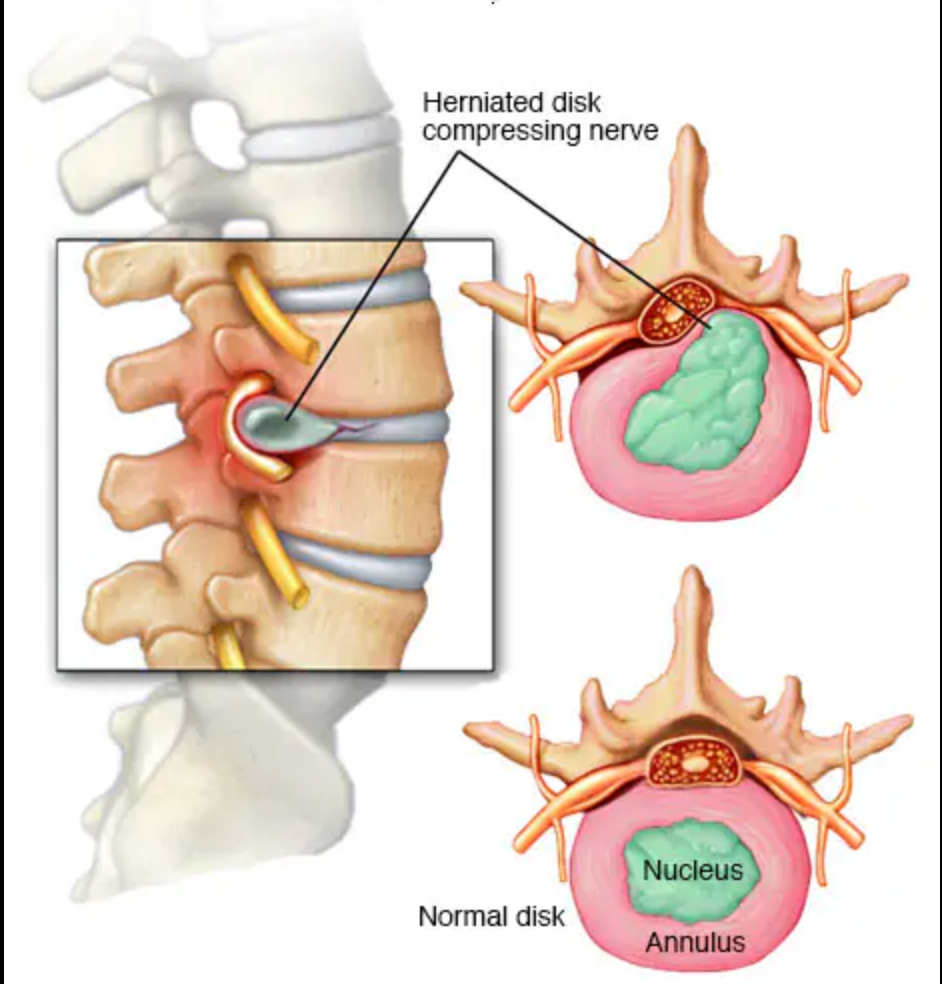

- Degenerative disc disease

- Recurrent disc herniation

- Lumbar canal stenosis with instability

- Nerve compression is relieved

- The damaged disc is removed